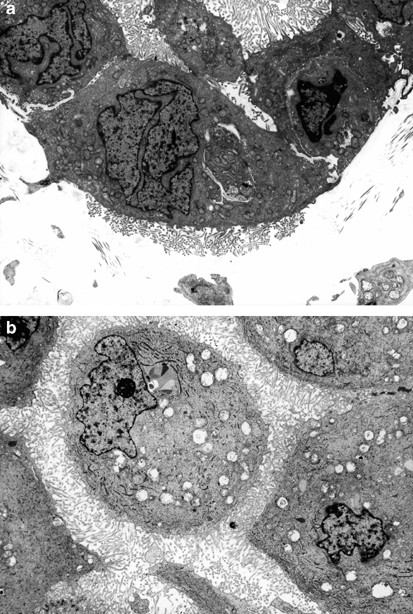

Figure 7

(a) The basal lamina, which is apparent on both the right and left sides of this figure, appears absent in the center, probably as a result of the proliferation of microvilli, which gives the impression of invading into the adjacent stroma (× 7600). (b) The entire cell membrane of the mesothelioma cell in the center of the figure is covered by microvilli (× 5300).